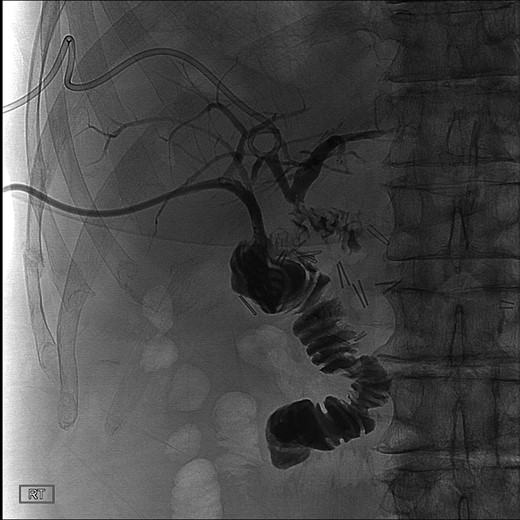

During this operation, the porta was dissected and the common and proper hepatic arteries were identified and preserved. We were unable to palpate the previously placed percutaneous biliary catheters due to the high placement above the hilum at the level of multiple clips. We transected the CBD distally and removed numerous clips, finally noting bile drainage, but were unable to identify a cholangiogram catheter. We then identified a second tubular structure more lateral to the duct. We elected to transect this tissue, identifying a second extrahepatic bile duct. The anterior percutaneous catheter was identified proximally within the duct. An on-table cholangiogram with fluoroscopy was performed noting two separate extrahepatic biliary systems, draining the right and left lobes of the liver, respectively (Figs 3 and 4). Both distal ducts were ligated to definitively close the orifice to the duodenum and prevent spillage. A Roux limb of jejunum was created and anastomosed in a retrocolic fashion to the two separate hepatic ducts at the level of the hilum. A drain was placed, and there was no evidence of bile leakage.

Intraoperative cholangiogram of the right ductal system through the extrahepatic right CBD.